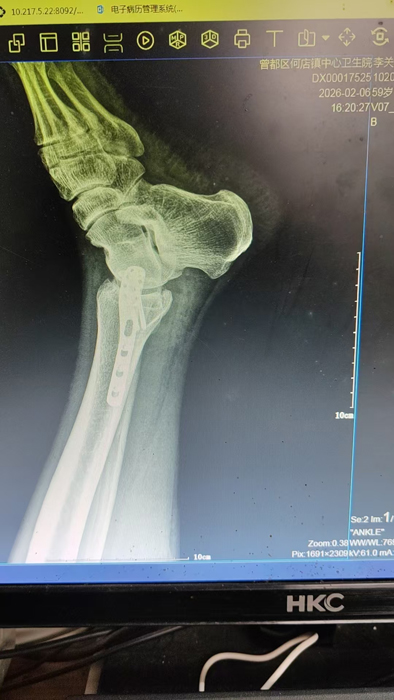

2月4日,何店鎮(zhèn)中心衛(wèi)生院接診一名左踝關(guān)節(jié)外傷患者,經(jīng)影像檢查,確診為左脛、腓骨下段骨折。外科醫(yī)生姜穩(wěn)迅速完成術(shù)前檢查及病情評估,并與患者及家屬深入溝通治療方案。在患者強烈要求于本院進行手術(shù)的情況下,為最大限度保障手術(shù)質(zhì)量與安全,該院特邀請醫(yī)共體牽頭單位——曾都區(qū)人民醫(yī)院脊柱創(chuàng)傷外科專家團隊前來指導(dǎo)。

本次幫扶由曾都區(qū)人民醫(yī)院脊柱創(chuàng)傷神經(jīng)外科主任徐三軍帶隊,專家團隊抵達后立即完成手術(shù)風險評估及術(shù)前準備。手術(shù)過程中,徐三軍主任嚴格規(guī)范完成各項手術(shù)操作,并同步結(jié)合手術(shù)步驟,為該院外科醫(yī)師詳細講解骨折手術(shù)的關(guān)鍵要點、操作技巧、術(shù)中注意事項及術(shù)后康復(fù)要領(lǐng)。通過“手把手”的實戰(zhàn)帶教,專家將豐富的手術(shù)經(jīng)驗與規(guī)范的診療思路傾囊相授,讓該院醫(yī)護人員在實操中學(xué)習(xí),在過程中成長。